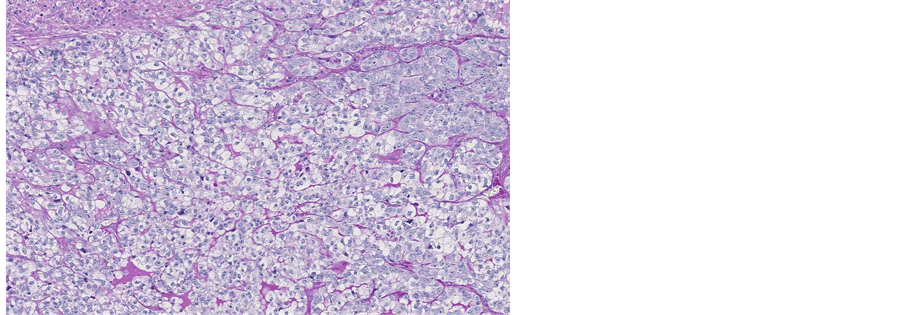

The Periodic acid-Schiff (PAS) staining for glycogen was positive (Figure 3), and Periodic acid-Schiff-diastase (PAS-D) staining for mucus was negative (Figure 4).

Figure 4. Microscopic appearance of the endometrial tissue from curetting specimen-clear cell carcinoma, Periodic Acid-Schiff- diastase (PAS-D) staining, ×10.